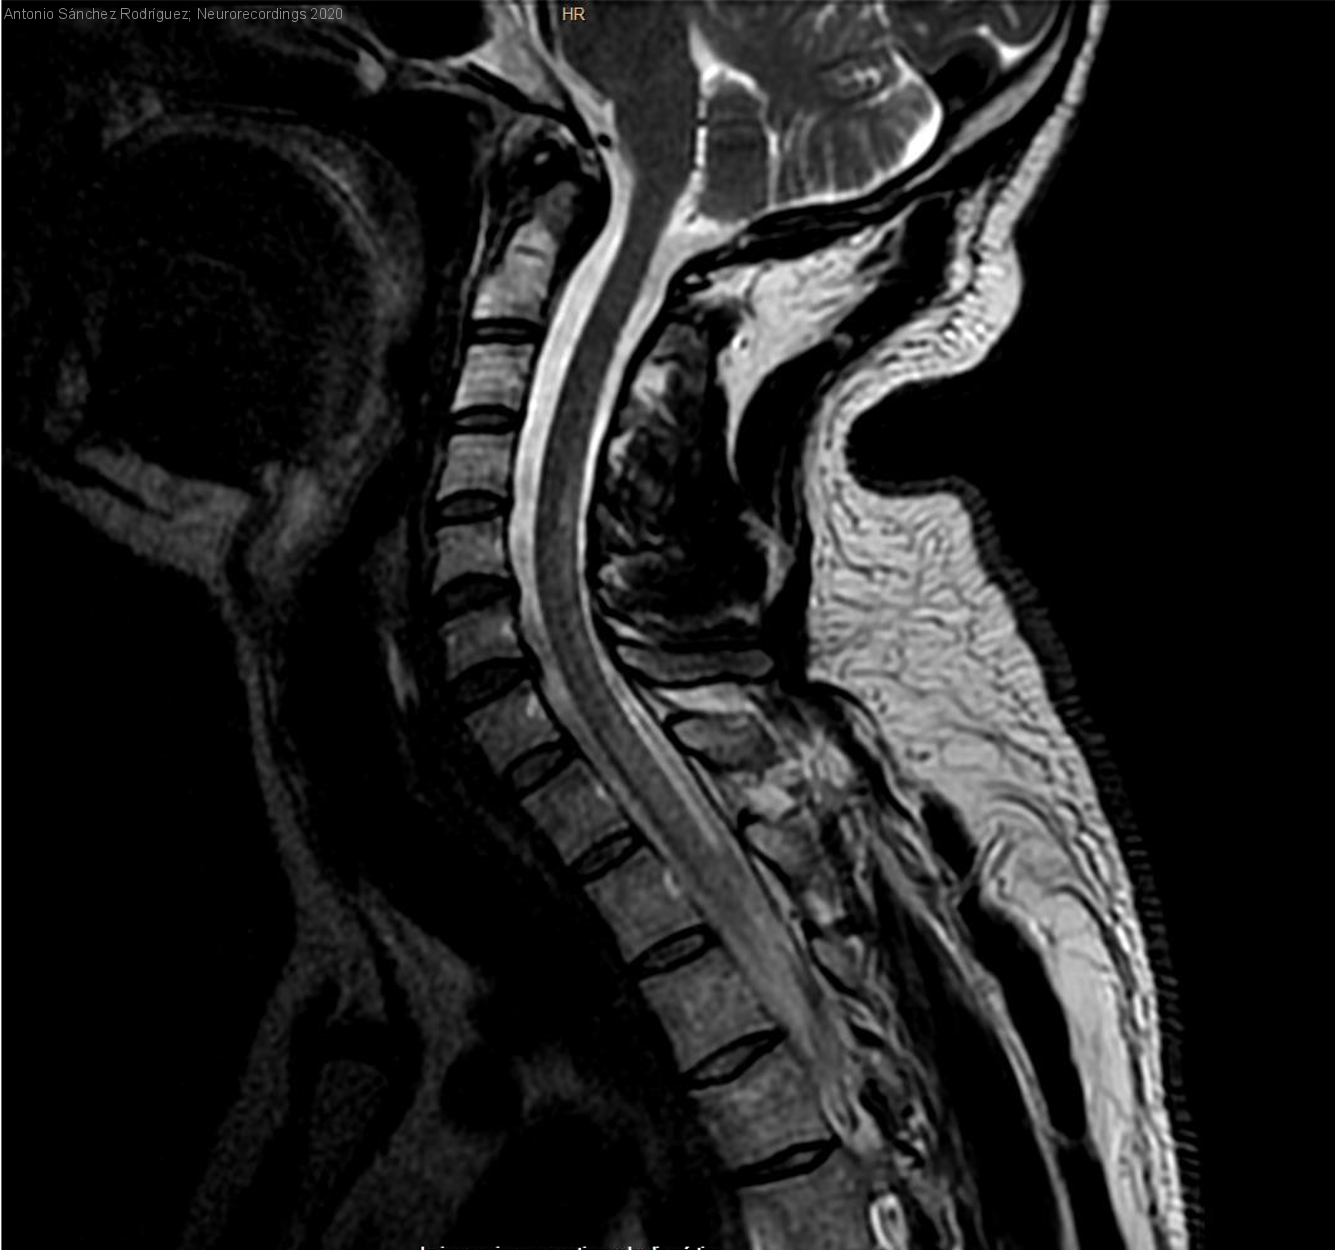

Diagnóstico final: Mielopatía cervico-dorsal secundaria a accidente descompresivo.

Varón de 41 años, buceador profesional sin otros antecedentes de interés que, tras una inmersión profunda y posterior ascenso rápido, sufre un cuadro de paraparesia con alteración esfinteriana, compatible con un síndrome medular agudo.